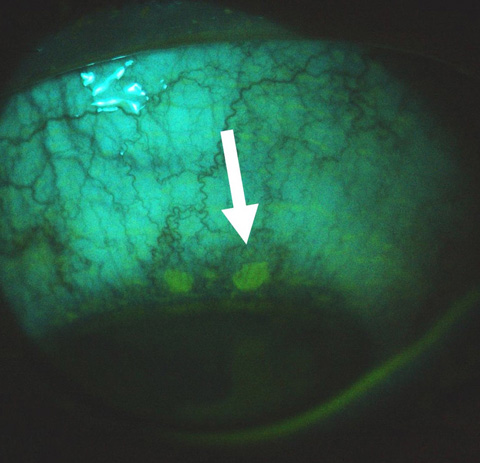

Conjunctival ulcers: a rare feature of ocular herpes simplex virus infection